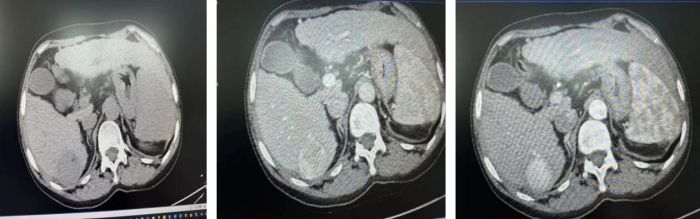

近日,思南县人民医院MDT团队精准施策,为一名59岁乙肝小三阳、肝硬化合并肝细胞癌患者实施腹腔镜下肝S6段切除术,患者术后顺利康复出院。